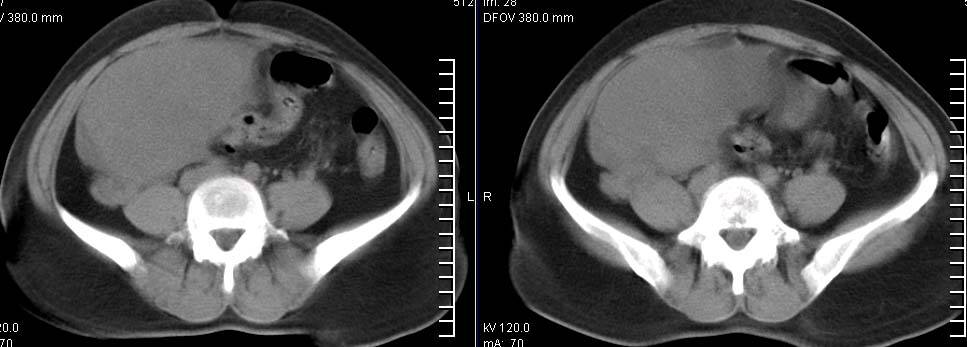

标题: CT9722:卵巢巨大占位,约10*18*21CM大小

卵巢巨大占位,约10*18*21cm大小

肿瘤的密度有点高.和子宫差不多?且和子宫相连呢?我考虑来源于子宫,子宫巨大子宫肌瘤可能性大!(局部有坏死?)

囊腺瘤不管是浆液性,还是黏液性的,液体成分应该占的比例很大吧!!这个病灶其实是个实性肿块,更看不到囊腺瘤所能见到的分隔??请笔者提供ct值?望大家再仔细分析??

右侧卵巢的巨大占位,病灶大部分呈实性,以恶性可能大。

右侧附件区巨大囊性肿块,边缘光滑,密度较高,左侧缘由多个低密度区,首先考虑囊腺瘤可能。